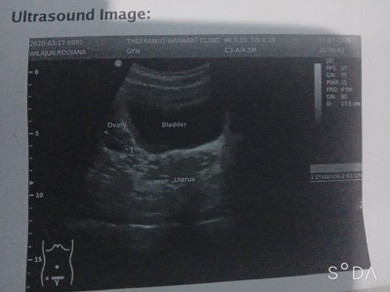

ภาพอัลตร้าซาวน์ภาพนี้ ตั้งครรภ์ไหมค่ะ. หรือว่าไม่ตั้งครรภ์

รูปไม่ชัดเลยค่ะ มีกระเพาะปัสสาวะ มดลูก รังไข่ ส่วนมีหรือไม่มีน้อง ต้องถามคุณหมอค่ะ

ในมดลูกไม่เห็นอะไรเลยค่ะแม่ หมอได้บอกอะไรไหมค่ะ